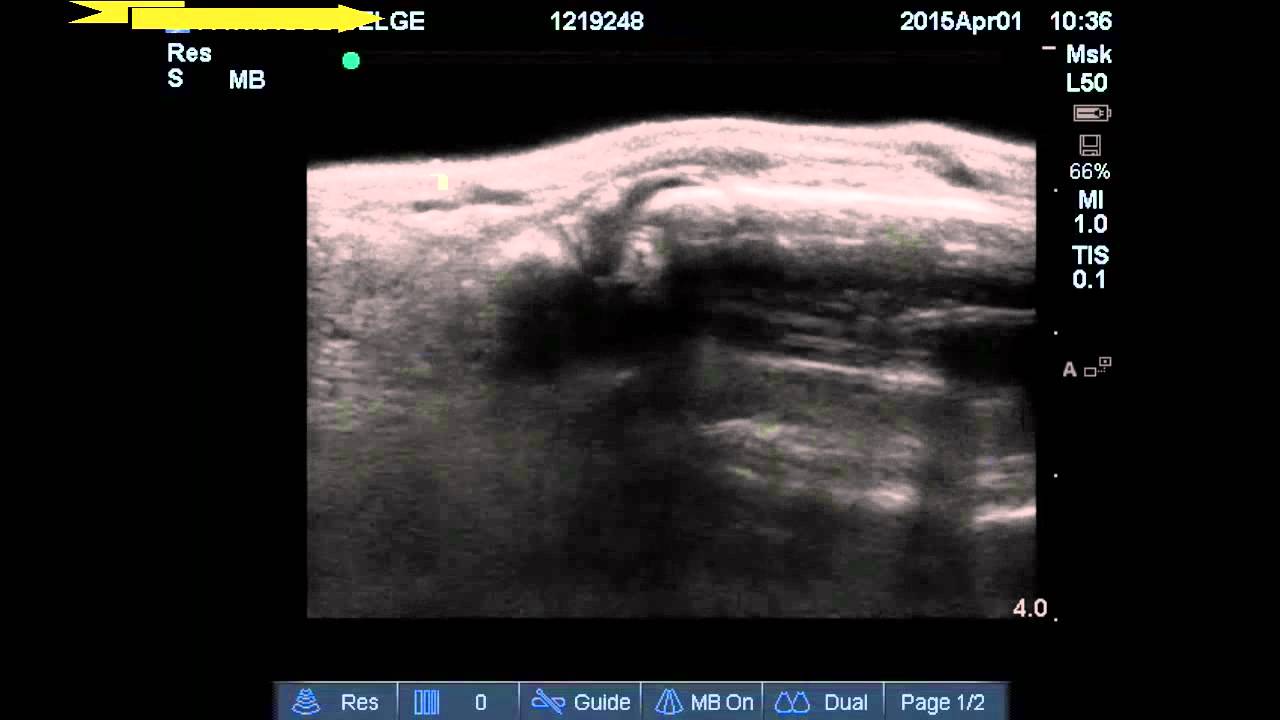

The ultrasound findings of the ingested beads can demonstrate an intraluminal cystic structure. Furthermore, given the radiolucency of water beads ultrasound should be considered in the diagnostic workup to evaluate a small. Here, we describe an infant with water bead ingestion whose symptoms resolved with conservative management, using ultrasound as. 3 cases describe the use of a ct scan which can.

(PDF) A case of ingested water beads diagnosed with pointofcare Water Beads Ultrasound The ultrasound findings of the ingested beads can demonstrate an intraluminal cystic structure. Furthermore, given the radiolucency of water beads ultrasound should be considered in the diagnostic workup to evaluate a small. Here, we describe an infant with water bead ingestion whose symptoms resolved with conservative management, using ultrasound as. 3 cases describe the use of a ct scan which. Water Beads Ultrasound.